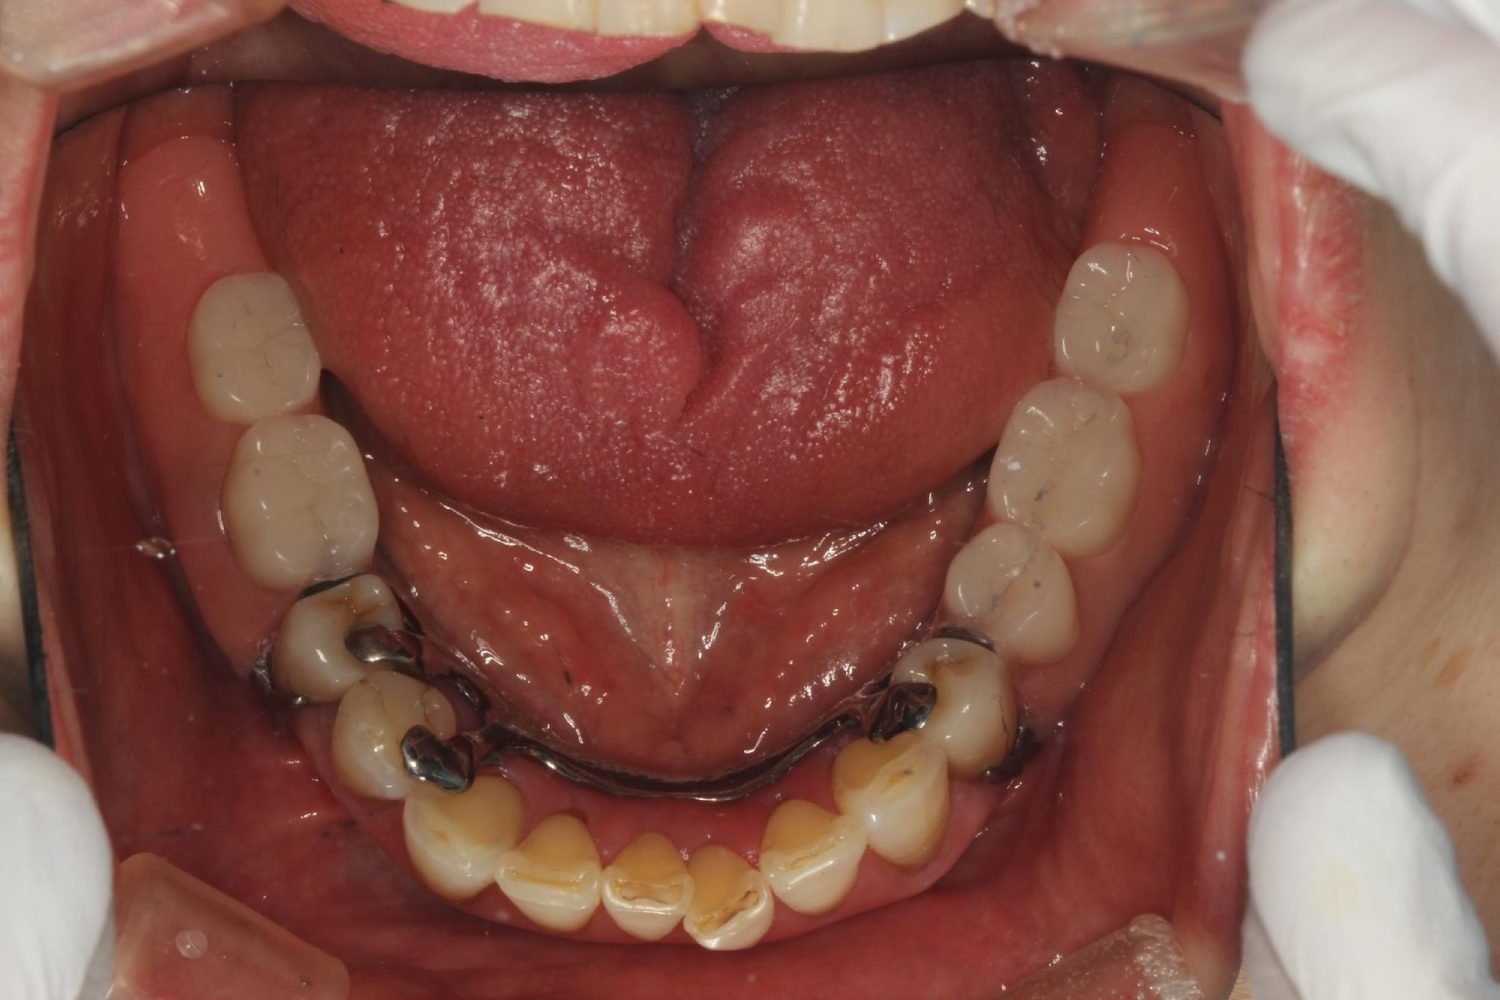

インプラント治療の症例紹介⑤

Before

After

主訴

歯肉腫脹、咬めるようにしたい

治療内容

重度歯周病により全ての残存歯保存不可能な状態。上下顎ボーンアンカードブリッジによる咬合再構成。

治療費

12,621,400円(税込)

治療期間

22ヶ月

通院回数

28回

想定されたリスク

※上部構造の形態が複雑になるため清掃が難しくなる、インプラント周囲炎の恐れがありました。

濱 仁隆先生

浜歯科

上顎8本下顎7本のインプラント体埋入によるボーンアンカードブリッジ。